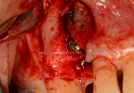

Clinical Cases

• Case1

• Case2

• Case3

• Case4

• Case5

• Case6

• Case7

• Case8

• Case9

• Case10